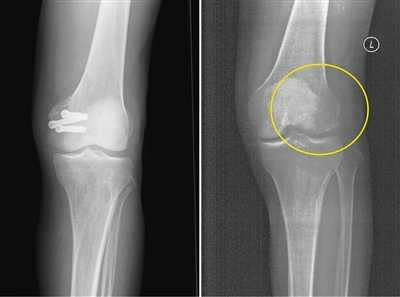

左為使用金屬螺釘后拍攝的影像,右為使用蠶絲螺釘后拍攝的影像。受訪者供圖

在長期的臨床應(yīng)用過程中,金屬材料逐漸顯現(xiàn)出三大缺陷:一是金屬內(nèi)固定往往需要二次手術(shù)取出,大大增加了患者的痛苦及經(jīng)濟負擔(dān)。二是金屬的力學(xué)強度遠遠超過骨骼,導(dǎo)致應(yīng)力遮擋,影響骨折愈合。此外,使用部分金屬材料術(shù)后無法進行CT和磁共振拍攝;即使鈦合金材料可以進行檢查,也存在明顯的偽影,螺釘周邊模糊一團,嚴重影響影像觀察的效果。

今年5月,患者張強(化名)不慎扭傷,造成左股骨遠端骨折。由于骨折部位靠近關(guān)節(jié)面,使用金屬螺釘固定時應(yīng)力過大,會影響骨折愈合;1年后還需要手術(shù)將金屬螺釘取出,可能造成二次創(chuàng)傷;颊呷朐褐,團隊經(jīng)過詳細探討病情、細致閱片后認為,該患者符合可降解蠶絲螺釘固定的適應(yīng)證。術(shù)中團隊對該患者使用可降解蠶絲螺釘固定骨折塊,術(shù)后的CT片中沒有任何偽影,可以清晰地看到骨折塊已經(jīng)完全復(fù)位,并且解除了患者二次手術(shù)取出螺釘?shù)呢摀?dān)和困擾。